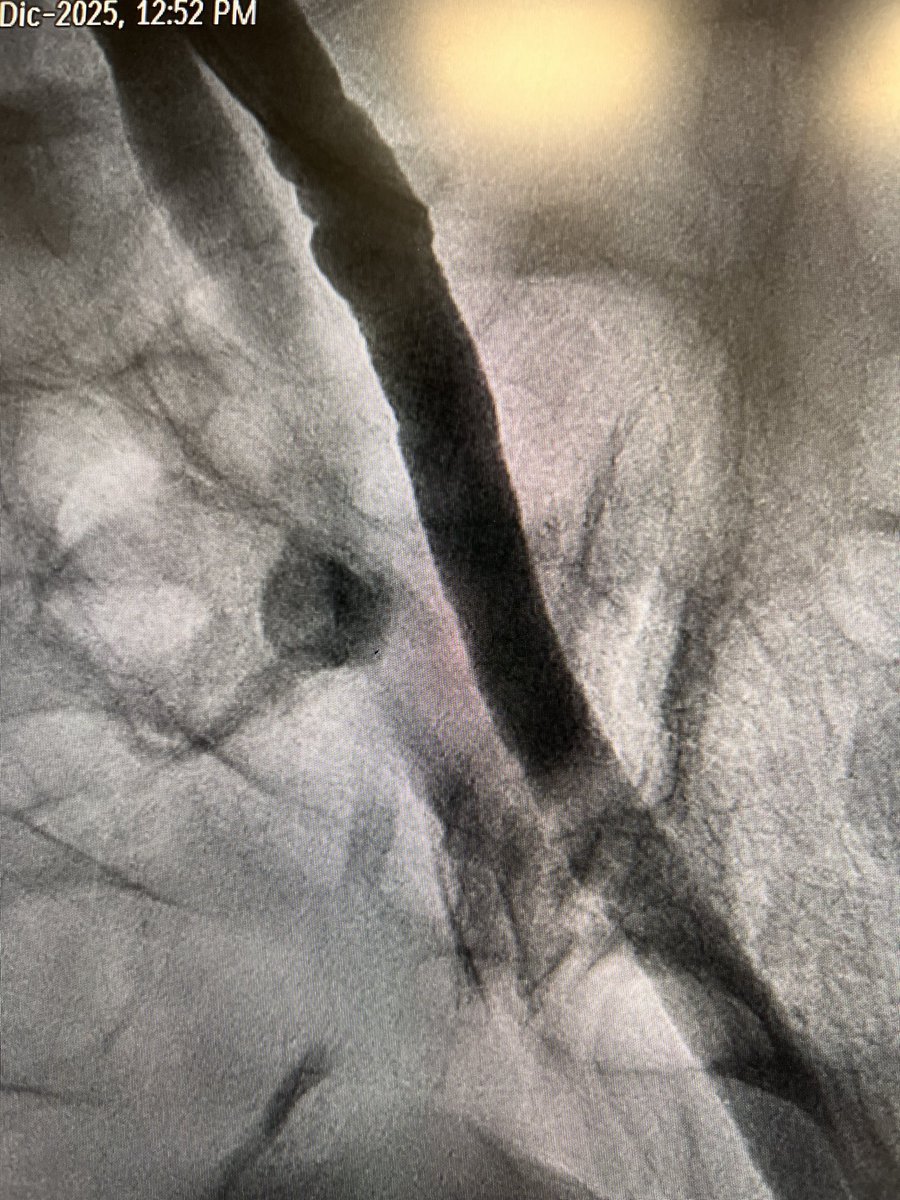

👍 “A Contemporary Algorithm to Guide Percutaneous Coronary Intervention in High-Risk Spontaneous Coronary Artery Dissection” 🤜🤛: 🔗 hmpgloballearningnetwork.com/site/jic/origi……